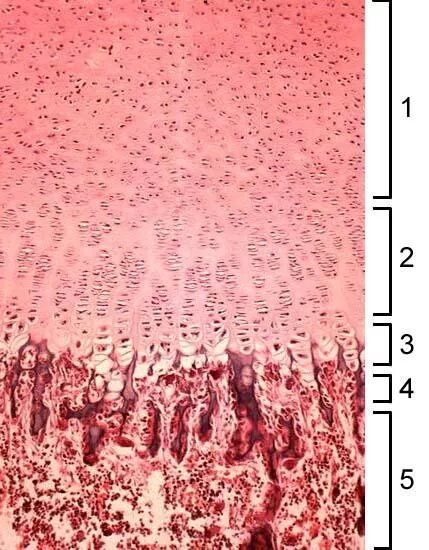

Гистология ростов на дону